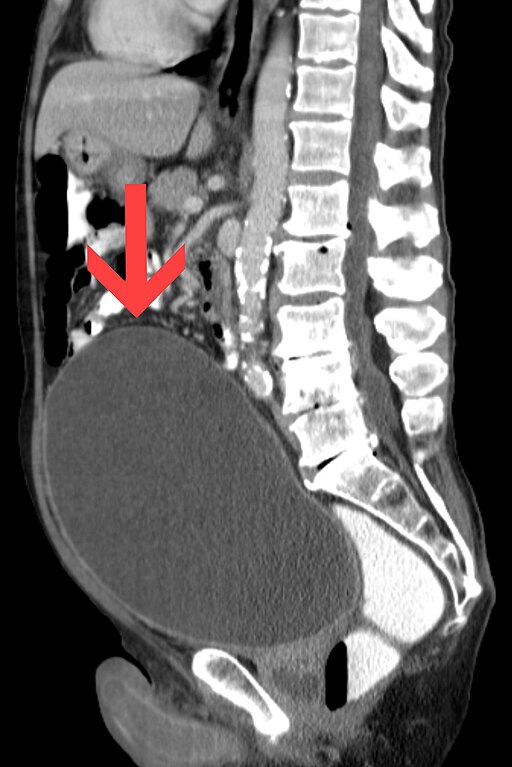

DefinitionHarnverhalt

(Ischurie ) Unfähigkeit zur spontanen Blasenentleerung (Miktion) trotz gefüllter Harnblase.

Harnverhalt.jpg von Hellerhoff, CC BY-SA 3.0, via Wikimedia Commons

Man unterscheidet einen akuten Harnverhalt

Zu den typischen Ursachen zählt die benigne Prostatahyperplasie